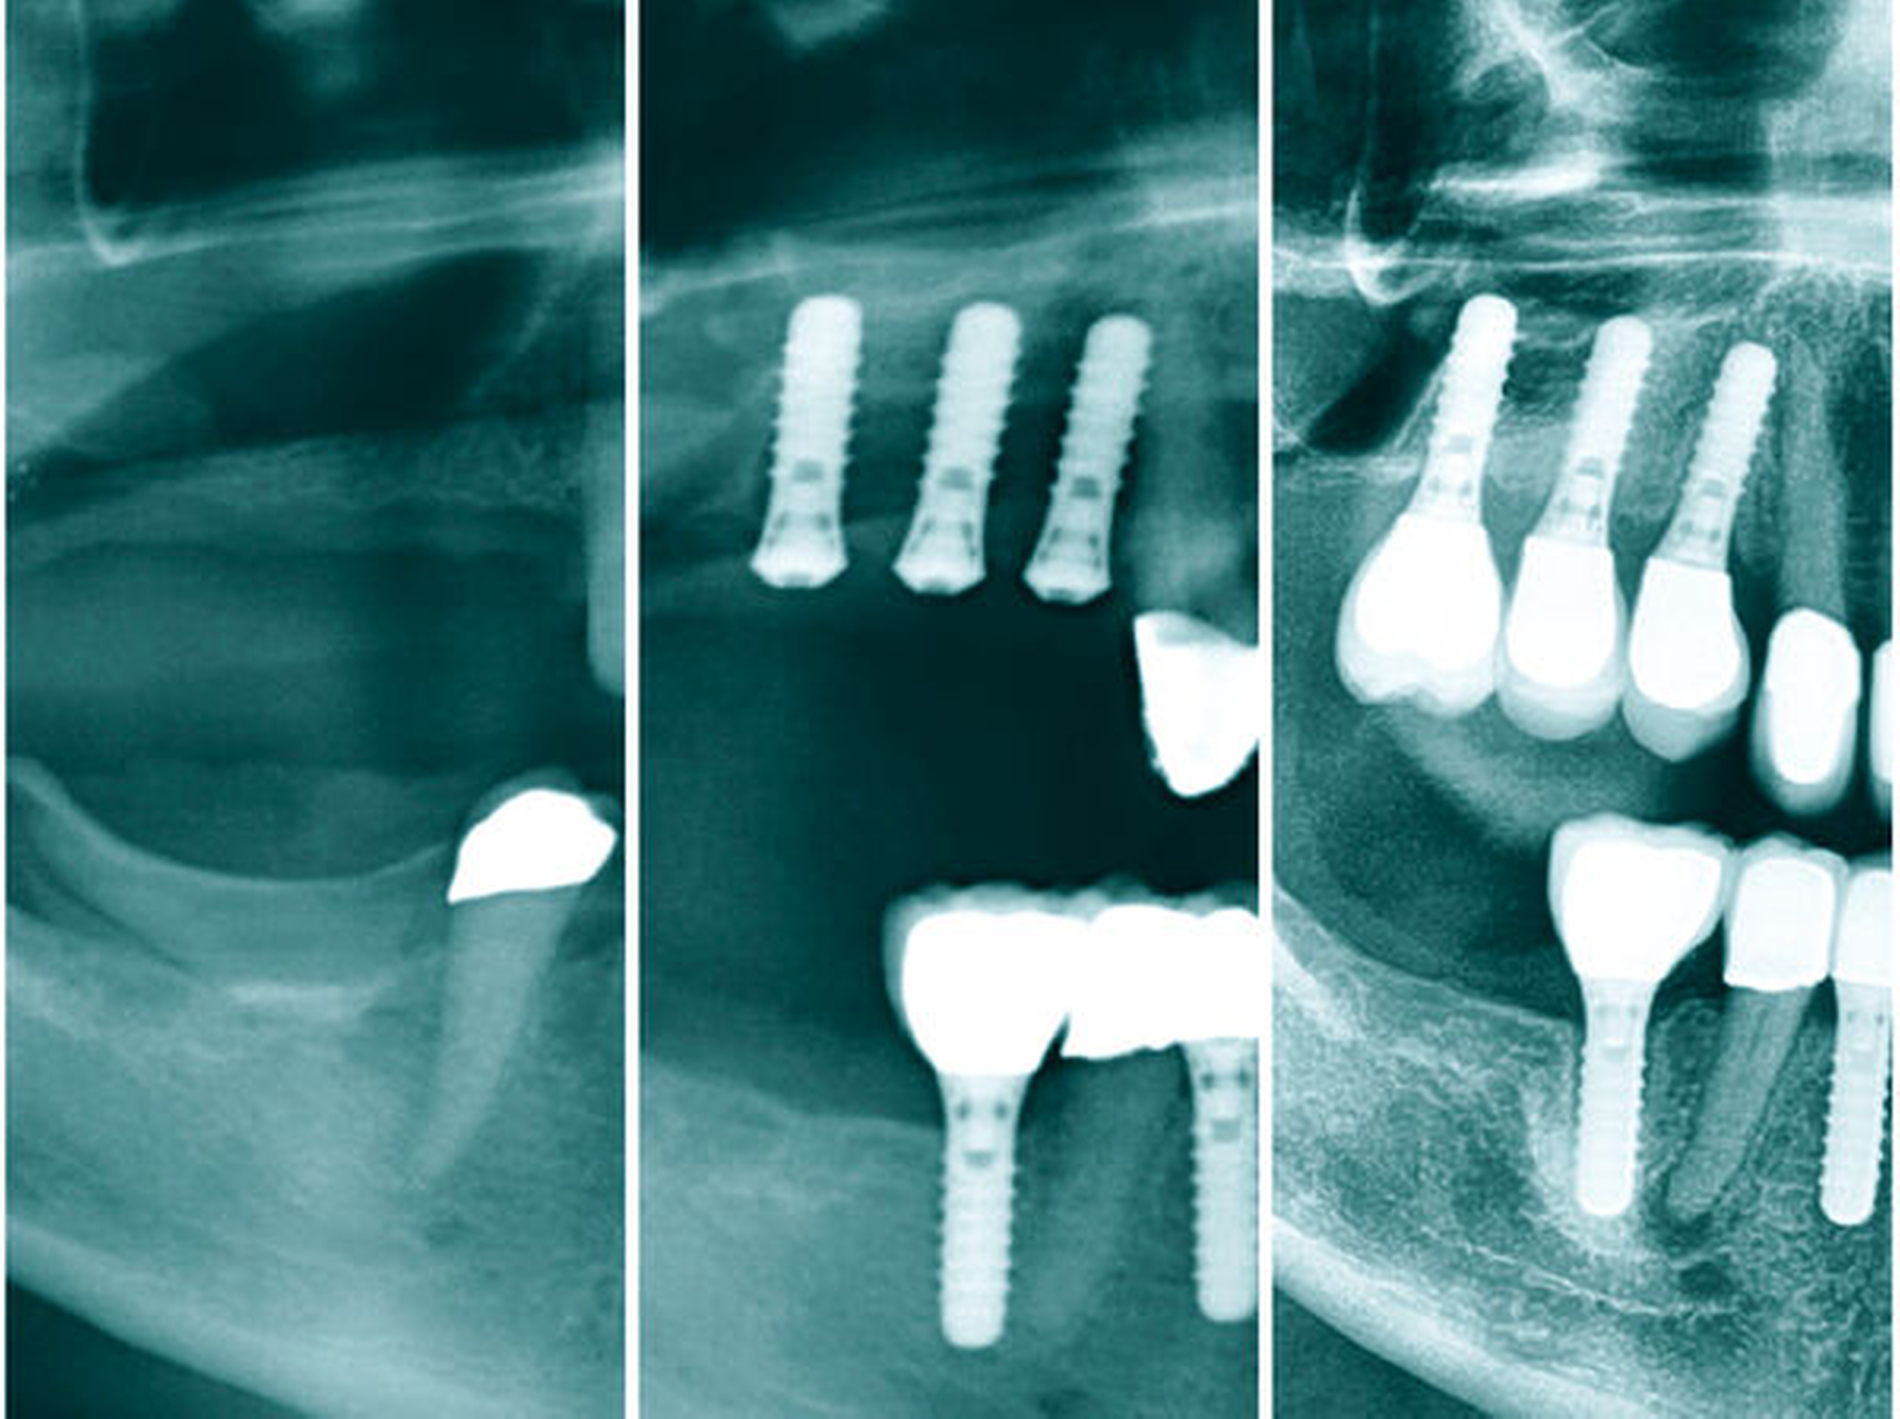

In den Abbildungen 6 bis 9 sind mehrere Fälle mit langem Beobachtungszeitraum dargestellt. Beachtenswert ist vor allem der zu beobachtende vollständige Umbau des Knochens inklusive der Ausbildung einer neuen Kompakta. Die augmentierten Bereiche sind nach wenigen Jahren nicht mehr als solche zu erkennen. Die Arbeit mit autologem Knochen ist insbesondere für die Patientengruppe interessant, die bevorzugt nach biologisch sicher verträglichen Behandlungen sucht. Dieser Trend nimmt unseren Beobachtungen nach stetig zu. n